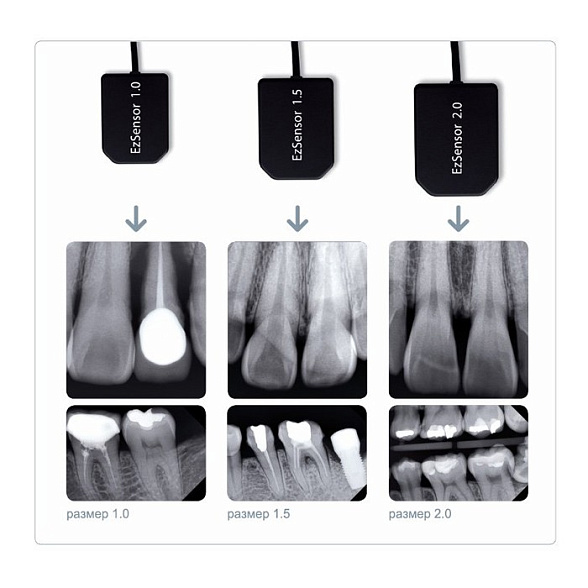

- Комфорт для пациента: Небольшой и эргономичный датчик (сенсор) минимизирует дискомфорт во время размещения в полости рта, особенно у пациентов с выраженным рвотным рефлексом.

| Активная площадь датчика | Различные размеры (например, стандартный размер 1, приближенный к пленке №2) |